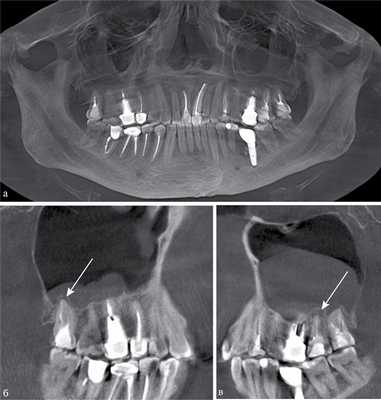

По результатам нашего исследования у 24 (14,5%) пациентов были обнаружены признаки хронического периодонтита в области премоляров и моляров верхней челюсти (рис. 1). Глубокий кариес был диагностирован у 4 (2,4%) пациентов, кисты верхней челюсти в области корней премоляров и моляров визуализировались в 6 (3,6%) случаях.

Рис. 1. КЛКТ. Панорамная (а) и мультипланарные реконструкции правого (б) и левого (в) верхнечелюстных синусов пациента М., 37 лет. Диагноз: двусторонний одонтогенный хронический верхнечелюсной синусит. Отмечаются КТ-признаки хронического гранулематозного периодонтита зубов 1.8, 2.7, 2.8 (в виде очагов деструкции у верхушек корней, округлой формы, с четкими ровными контурами). Нижние костные стенки синусов истончены, не прослеживаются в области периодонта зубов 1.8 и 2.8 (указаны стрелками). В нижнем отделе правого верхнечелюстного синуса определяется пристеночное мягкотканное образование гомогенной структуры с полицикличным верхним контуром. Левый верхнечелюстной синус субтотально заполнен мягкотканным содержимым гомогенной структуры с округлым верхним контуром.

Пломбировочный материал был обнаружен у 38 (22,8%) пациентов (рис. 2). Из них у 34 (20,4%) больных в подслизистом слое нижней стенки синуса, у 4 (2,4%) — в верхнем отделе у медиальной стенки синуса (рис. 3). У 8 (4,8%) пациентов диагностированы ошибки стоматологической имплантации: верхушка импланта была погружена в полость синуса, что стало причиной развития хронического одонтогенного верхнечелюстного синусита, а также осложнений в виде хронического полисинусита (n=4; 2,4%).

Рис. 2. МСКТ. Коронарная (а) и сагиттальная (б) реконструкции правого верхнечелюстного синуса пациента К., 29 лет. Диагноз: правосторонний одонтогенный хронический верхнечелюстной синусит. Корни зубов 1.6, 1.7 и 1.8 погружены в полость верхнечелюстного синуса. Состояние после эндодонтического лечения зубов 1.6 и 1.7, с выведением пломбировочного материала за верхушку небного корня 1.7. В области корней зубов 1.6 и 1.7 отмечается разрежение костной ткани с нечеткими неровными контурами (рентгенологические признаки гранулирующего периодонтита). В нижнем отделе синуса определяется пристеночное мягкотканное образование с полицикличным контуром, костные стенки синуса в данной области не прослеживаются.

Рис. 3. КЛКТ. Сагиттальная реконструкция, правый верхнечелюстной синус. Пациент У., 48 лет. Диагноз: правосторонний одонтогенный хронический верхнечелюстной синусит. Зубы 1.6 и 1.7 после эндодонтического лечения, отмечается выведение пломбировочного материала за верхушки корней зуба 1.6 (материал располагается в костной ткани альвеолярного отростка и в подслизистом слое синуса). Определяется разрежение костной ткани в области корней 1.6 и 1.7, костная стенка синуса в данной области не прослеживается (стрелка). В нижнем отделе синуса определяется утолщение слизистой оболочки до 10 мм, в верхнемедиальном отделе синуса визуализируется инородное тело неправильной формы металлической плотности (соответствует фрагментам пломбировочного материала).